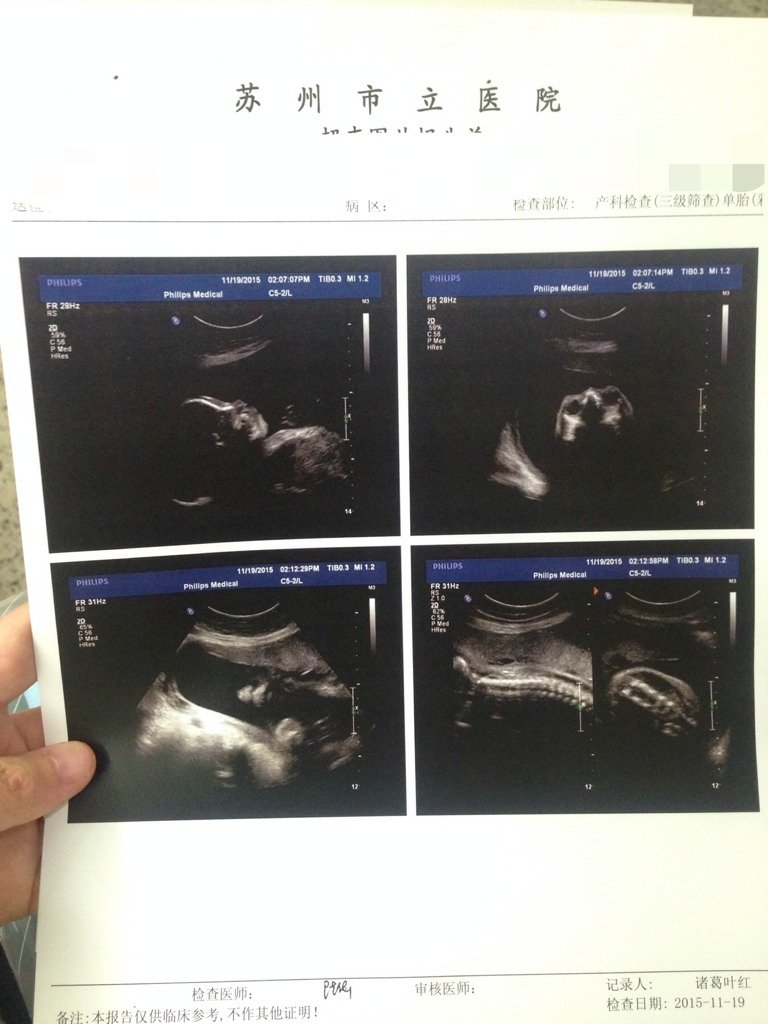

怎么觉得不是三维,都看不清楚的,虽比不上四维,但是这是普通B超嘛 怎么觉得不是三维,都看不清楚的,虽比不上四维,但是这是普通B超嘛 点击展开 HealthLove 2015-11-19 16:22 为您推荐: 其他回答 正常就没事的 芳圈圈 2015-11-19 20:55 应该是普通的,不过只要宝宝健康,那不是比什么都好吗 天天爱你哦 2015-11-19 16:59 宝宝没问题就好 素颜依然狠美 2015-11-19 16:54 四维是排畸的 153*****239_BFyI 2015-11-19 16:42 是不清楚? 187*****160_mDez 2015-11-19 16:37 加载更多 相关问题 三维,四维,普通B超有什么不同?求解 18三体综合症通过三维四维彩超B超能看出来吗? 18三体综合症通过三维四维彩超B超能看出来吗?